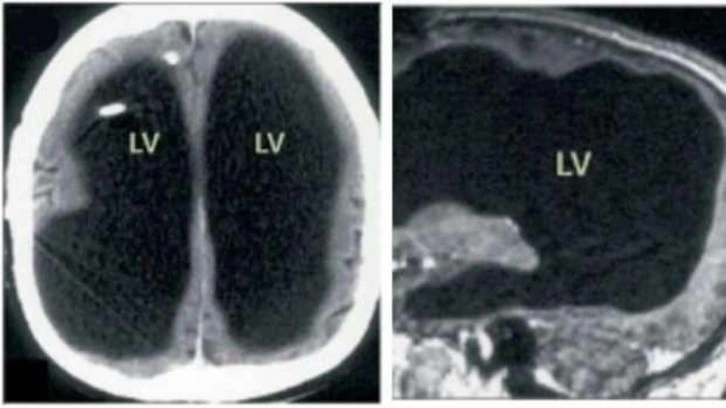

Bacağıyla ilgili şikayetlerle hastaneye başvuran 44 yaşındaki hastanın yapılan beyin taramasında, beyninin yarısından fazlasının olmadığı ortaya çıktı. Doktorlar, hastaya "hidrosefali" teşhisi koydu. Bu rahatsızlık, beynin büyük bir kısmının zamanla sıvıyla dolarak tahrip olmasına neden oluyor. Bilim insanları, hastanın çocukluk yıllarında hidrosefali nedeniyle stent takıldığını ancak 14 yaşında bu stentin çıkarılmasıyla beyninin aşınmaya başladığını düşünüyor. Son beyin taramasında durum fark edildiğinde 44 yaşında olan adamın, yaklaşık 30 sene yarım beyinle yaşadığı düşünülüyor. Buna rağmen adam, normal bir yaşam sürdürdü; ailesiyle vakit geçirdi, çalıştı ve gündelik aktivitelerini yerine getirdi. Şikayeti sırasında yapılan IQ testi, 84 olarak ölçüldü. Bu değer, ortalamanın biraz altında kabul edilse de hastanın günlük yaşamını sürdürebilmesi bilim dünyasını şaşırttı. Bilişsel psikolog Axel Cleeremans, bu vakayı değerlendirerek, beynin yalnızca belirli bir bölgesinin bilinçten sorumlu olduğu görüşünün değişebileceğini belirtti.